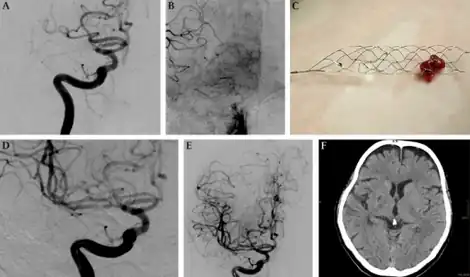

| Mechanical thrombectomy using a Solitaire stent-a)Injection of internal carotid artery shows embolic occlusion b)leptomeningeal collaterals visualized c)solitaire stent loaded with thrombus d,e)DSA with injection of right ICA f) 22 months after there is a small post-ischemic scar | |